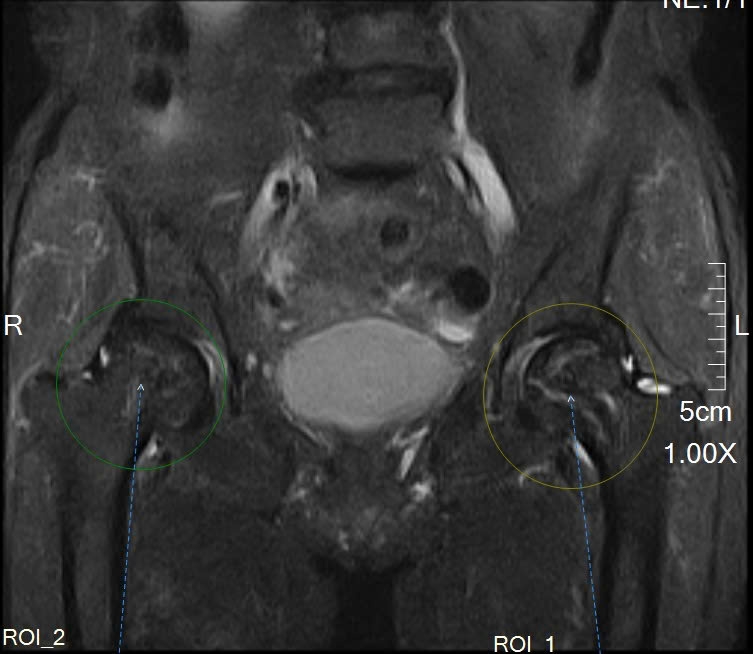

🍎Sau khi thăm khám lâm sàng, bác sĩ chỉ định chụp cộng hưởng từ (MRI) khớp háng để đánh giá chi tiết tình trạng xương và khớp.

Kết quả chụp MRI cho thấy dấu hiệu hoại tử chỏm xương đùi – một tổn thương khó phát hiện nếu chỉ chụp X-quang ở giai đoạn sớm. Nhờ hệ thống máy chụp cộng hưởng từ MRI hiện đại tại Hồng Hoàng, các bác sĩ đã phát hiện bệnh kịp thời, từ đó tư vấn hướng điều trị phù hợp cho bệnh nhân.